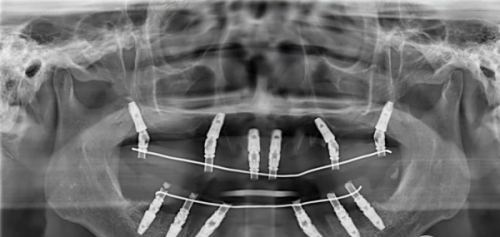

规模与设备完善:门诊拥有完善的诊疗区域,配备了精良的口腔诊疗设备,如德国卡瓦CBCT、3Shape Trios口扫仪、显微根管系统等。科室设置涵盖了种植牙、牙齿矫正、牙齿修复、儿童齿科、基础治疗等全领域需求,能够满足不同患者的口腔诊疗需求。

种植牙项目优势:在种植牙项目上,有多种种植体可供选择,如韩国登腾2680 - 5980元起一颗,瑞士ITI7980 - 25000元起一颗。门诊采用数字化导板种植牙技术,CBCT + 口扫数据5分钟生成3D导板,种植误差≤0.1mm,AI数字化导板支持当天戴牙,全口种植手术时间缩短至3小时,大大提高了种植的精细度和效率。

牙齿矫正项目亮点:牙齿矫正项目涵盖金属托槽6500 - 9800元起,隐适美隐形矫正32800元起。利用3Shape Trios口扫仪即刻呈现矫正后动态结果,可提前“预见”笑容,5分钟生成动态矫正图,患者可预览终咬合,方便患者选择适合自己的矫正方案。